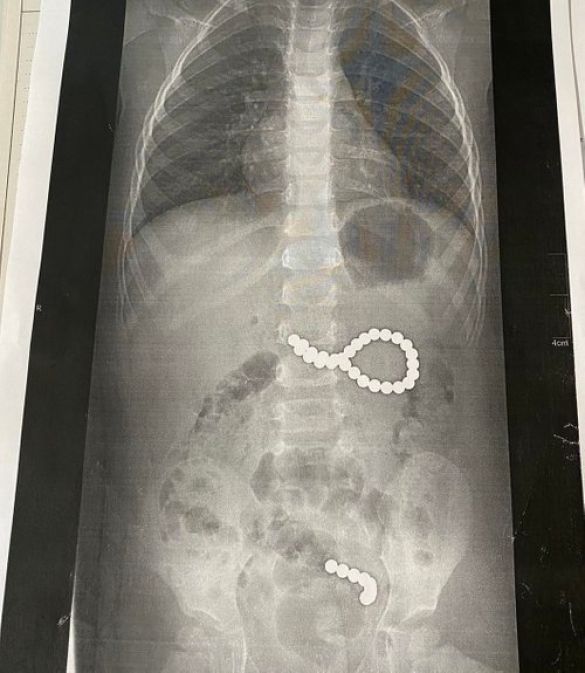

У суботу, 6 вересня, до львівської обласної дитячої лікарні ОХМАТДИТ госпіталізували дівчинку з Дрогобицького району, яка проковтнула 36 магнітних кульок від конструктора. Дев’ять кульок під дією магнітного поля утворили ланцюжок і потрапили в кишківник, ще 27 кульок утворили неправильне коло і потрапити в кишківник не могли. Дівчинку довелося терміново оперувати.

«Дев’ять кульок, які дитина проковтнула у п’ятницю, утворили ланцюжок, бо було сильне магнітне поле. І вони пройшли зі шлунка в тонкий кишківник. А ті 27 магнітних кульок, які дитина проковтнула у суботу, утворили неправильне коло і їх терміново треба було діставати. Кульки були діаметром 4 мм, найвірогідніше, з якогось конструктора», – каже Оксана Горбач.